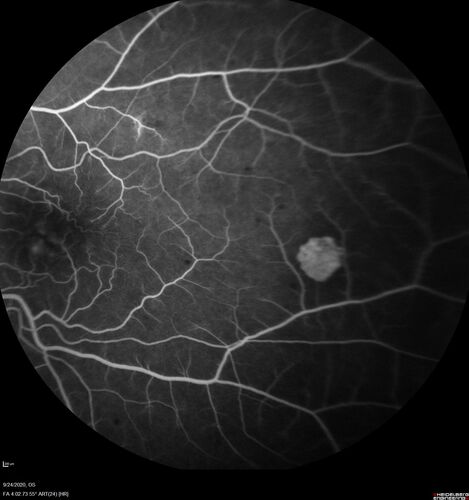

Elevated Episcleral Venous Pressure and Retinal Hemorrhages in both eyes

78 year old female with chronic red eye. The eyes are red all the time now. She is on Xeralto because of a history of blood clots in her lungs (2005 about). She has not had problems since. She has had floaters for many years. Ever since her eyes got funny she sees more floaters in both eyes. She had a brain scan over 6 months ago which was OK. She also had double vision when this first started which went away. She could not drive for a few months.

VA OD: Dcc20/32-1

VA OS: Dcc20/125

IOP: TP: OD:17 OS:16

Neuroimaging did not show a CC fistula